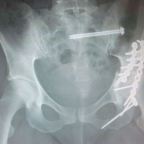

Gardening, Hip Trauma

Why is my glass half empty?

Fitness, Hip Trauma, Travel

Never give up!

A breakthrough at last!  Just when I (and my Physio) was thinking that after three major surgeries, extensive gluteal nerve … Continue reading Never give up!

The Main Event

Fitness, Gardening, Hip Trauma